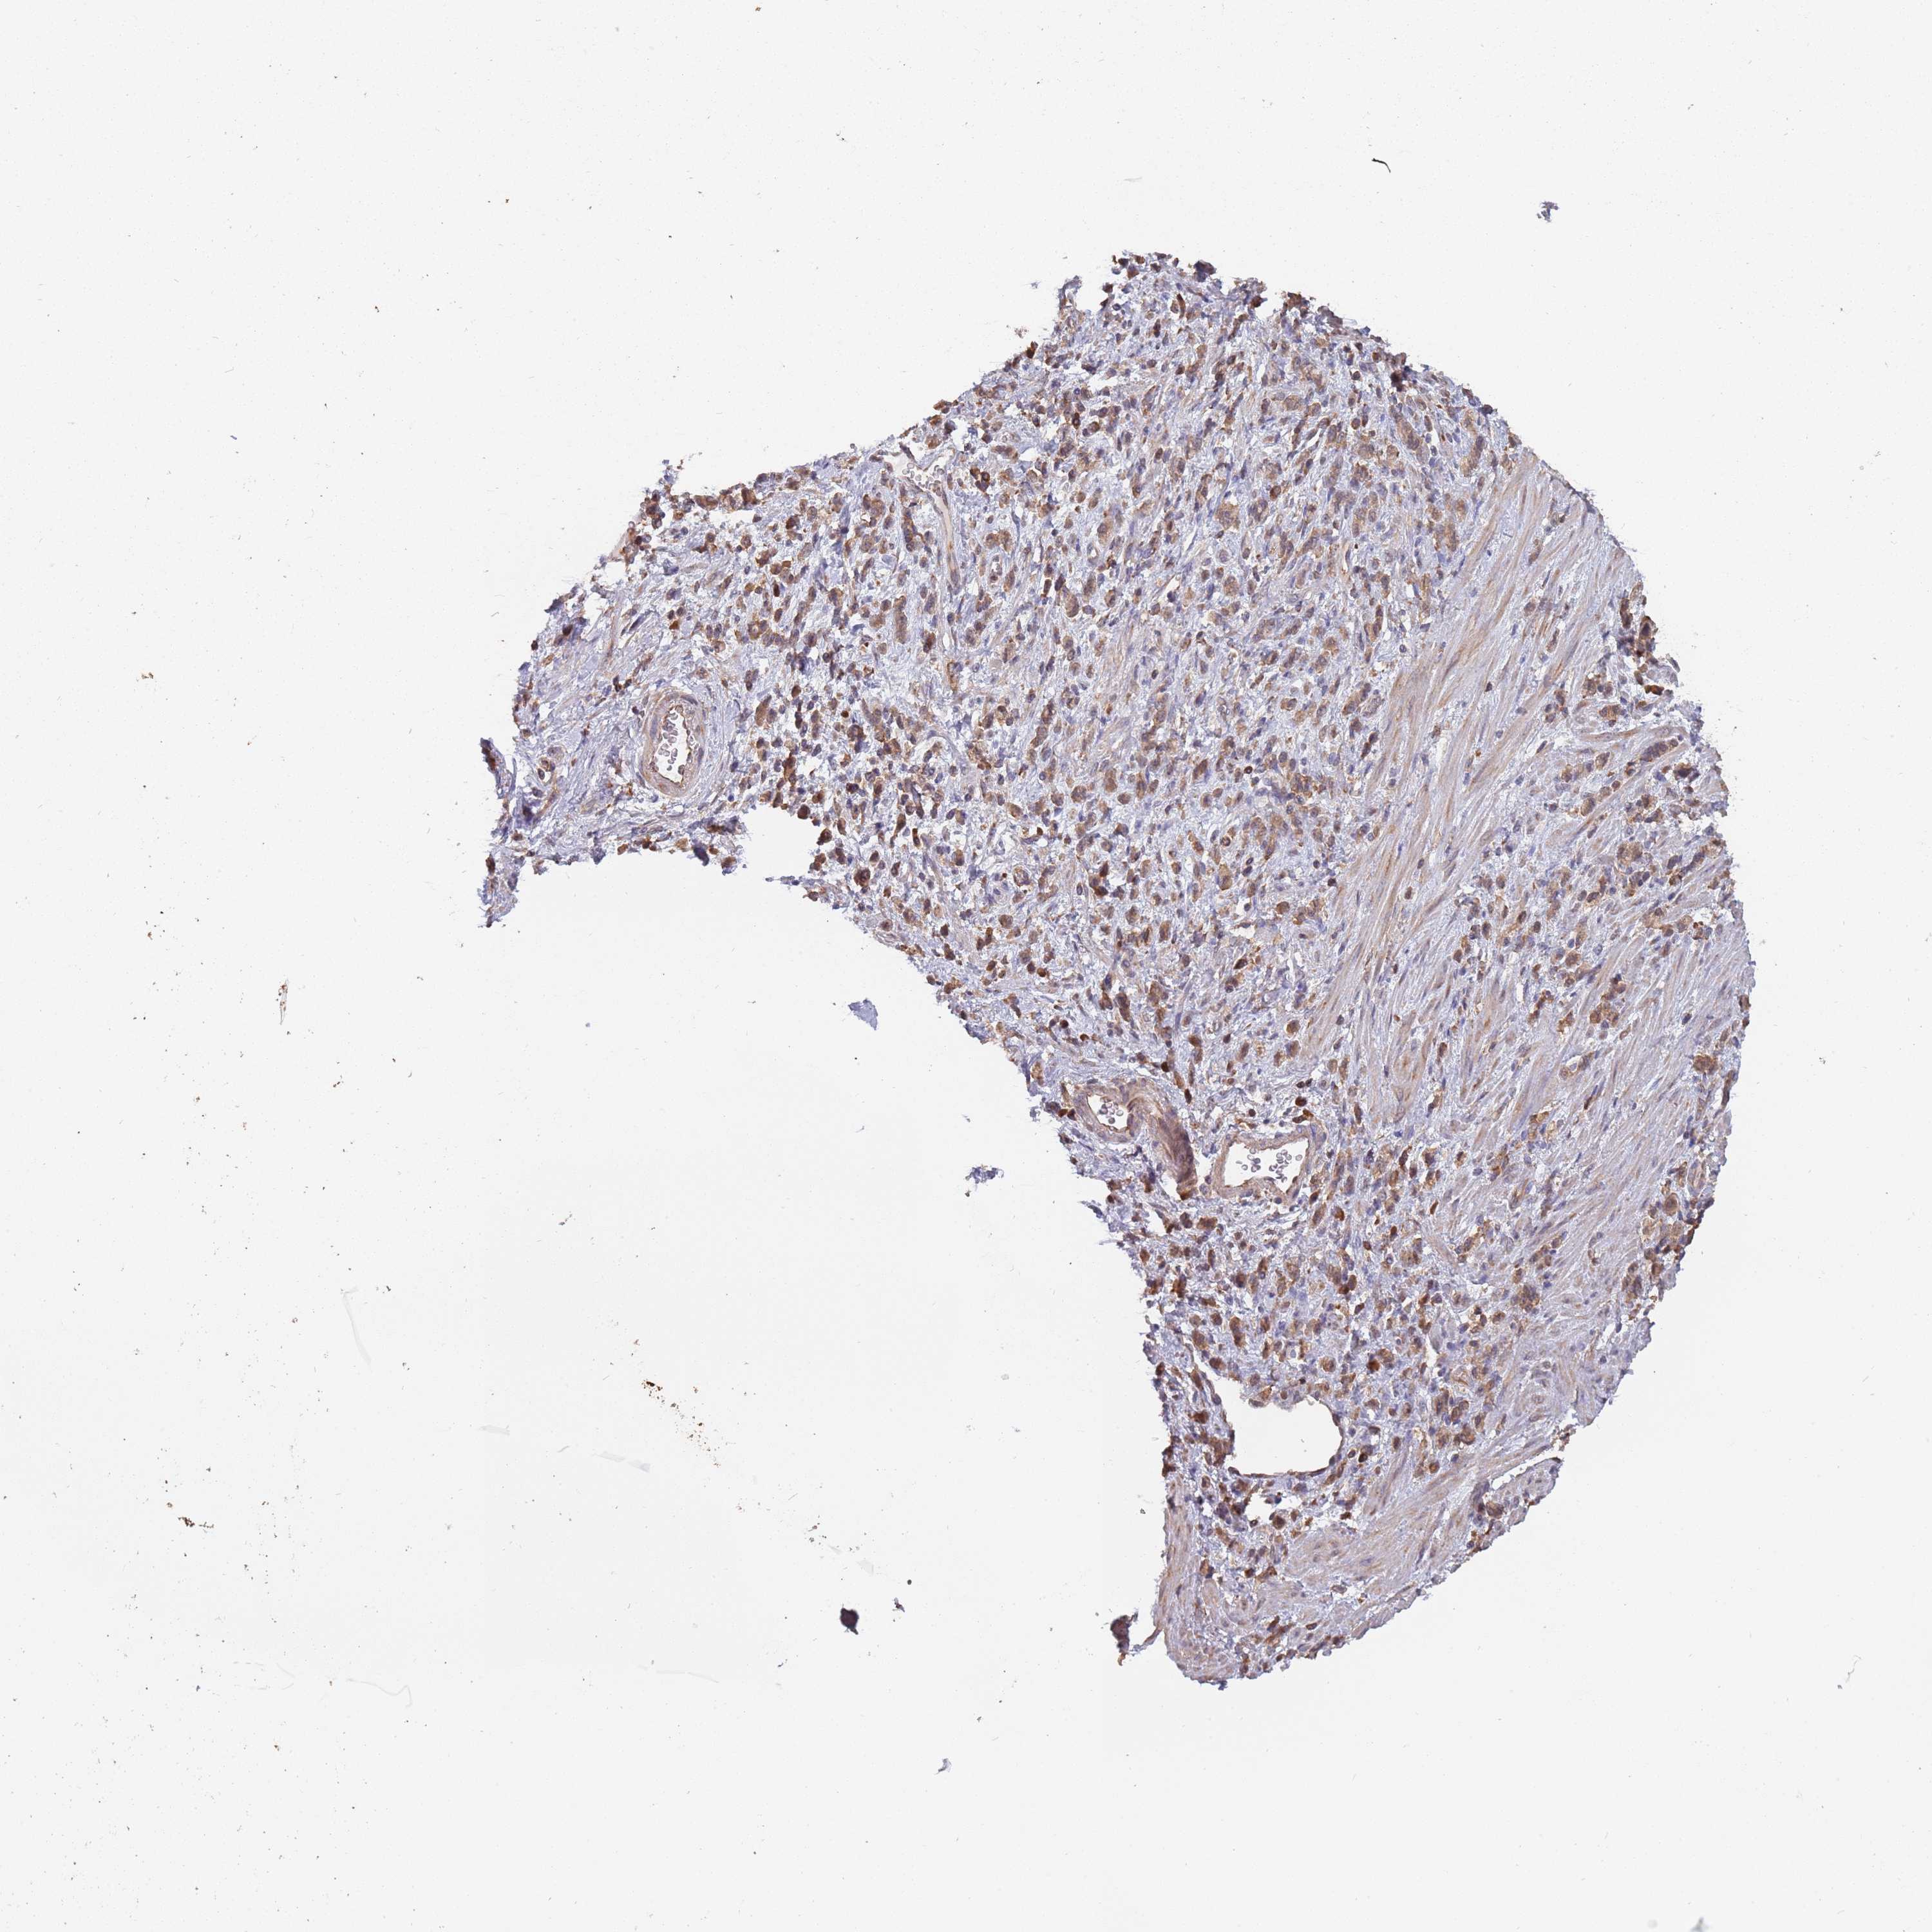

STOMACH CANCER - Protein expressioni

A mouse-over function shows sample information and annotation data. Click on an image to view it in a full screen mode. Samples can be filtered based on level of antibody staining by selecting one or several of the following categories: high, medium, low and not detected. The assay and annotation is described here.

Note that samples used for immunohistochemistry by the Human Protein Atlas do not correspond to samples in the TCGA dataset.

Antibody stainingi

Antibody staining in the annotated cell types in the current human tissue is reported as not detected, low, medium, or high, based on conventional immunohistochemistry profiling in selected tissues. This score is based on the combination of the staining intensity and fraction of stained cells.

Each image is clickable and will lead to virtual microscopy that enables deeper exploration of all samples and also displays staining intensity scores, fraction scores and subcellular localization as well as patient and tissue information for each sample.

Antibody HPA040924

Antibody HPA042539

Staining

High

Medium

Low

Not detected

Intensity

Strong

Moderate

Weak

Negative

Quantity

>75%

75%-25%

<25%

None

Location

Nuclear

Cytoplasmic/membranous

Cytoplasmic/membranous,nuclear

Adenocarcinoma, NOS

Adenocarcinoma, High grade